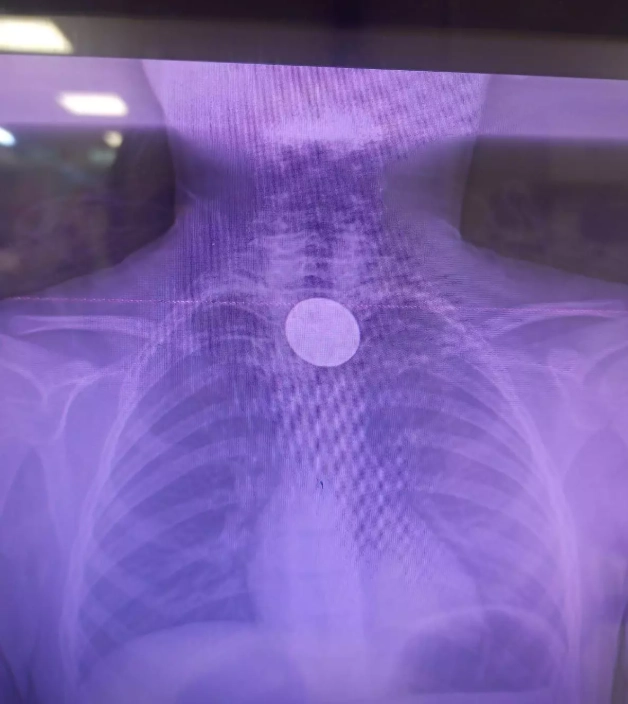

Siirt'te 8 yaşındaki çocuğun boğazına madeni 5 lira kaçtı. Hastaneye götürülen çocuğu doktorların titiz çalışması kurtardı.

Paylaşılan bilgilere göre 8 yaşındaki Y.K., yabancı cisim yutma şikayetiyle ailesi tarafından Siirt Eğitim ve Araştırma Hastanesine götürüldü.

Y.K.'nın yemek borusuna kadar ilerlediği tespit edilen madeni para, gastroenteroloji uzmanı Dr. Yaren Dirik ve kulak burun boğaz hekimi Yasin Gökçınar tarafından müdahale edilerek çıkartıldı.